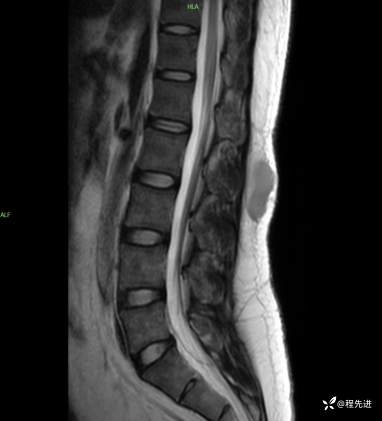

T2矢状位: